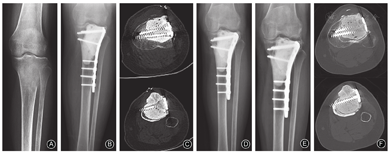

本组140例中,假体组46例(32.86%,46/140),结构性支撑组34例(24.28%,34/140),颗粒性植骨组49例(35%,49/140),其他组(植骨复合骨水泥、半关节假体、异体骨单髁关节置换)11例(7.86%,11/140)。

根据GTOC骨巨细胞瘤评分系统将假体组、结构性支撑组及颗粒性植骨组的129例回顾性评分(排除其他组的11例):GTOC评分≥9分者40例(35例假体置换、5例刮除),6~8分者46例(9例假体置换、37例刮除),<6分者43例(2例假体置换、41例刮除),3组GTOC评分的患者,不同手术方式的例数差异有统计学意义(χ2=70.067,P=0.000)。

GTOC评分≥9分的40例中,5例行刮除术,其中的4例行结构性支撑,1例行颗粒植骨;6~8分的46例患者中,37例行刮除术,其中26例行结构性支撑,11例行颗粒植骨;<6分的43例中,41例行刮除术,其中4例行结构性支撑,3组GTOC评分的患者,刮除患者不同重建方式的例数差异有统计学意义(χ2=32.803,P=0.000)。

由于GCT的局部生物行为具有侵袭性,复发率高15%~45%[15,16],但外科手术治疗依然是GCT的主要治疗措施。对于局部复发的治疗包括再次病灶内刮除或扩大切除,以避免肿瘤进展而致残。用高速磨钻联合异体骨移植或骨水泥填充的病灶内手术复发率可降至12%~14%[17,18]。扩大切除比病灶内刮除复发率低,但是存在功能重建的难题[19]。本组140例中,行肿瘤广泛切除、肿瘤假体置换46例(32.86%),结构性支撑(结构性植骨或骨水泥填充,应用或不应用内固定)34例(24.28%),颗粒性植骨组49例(35.00%),其他组(植骨复合骨水泥、半关节假体、异体骨单髁关节置换)11例(7.86%)。手术方式的选择主要依靠病变本身的特点、专家共识及术者的临床经验。

我们回顾分析140例胫骨近端GCT患者,发病部位单一,避免了不同部位的评分偏倚。按照GTOC系统评分,其中≥9分的患者40例、6~8分者46例、<6分者43例,行假体置换的比例分别为:87.5%、19.6%、4.7%,颗粒植骨的比例分别为:20%、29.7%、82.9%。表明GTOC评分影响手术方式的选择(χ2=70.067,P=0.000)以及刮除患者重建方式的选择(χ2=32.803,P=0.000)。